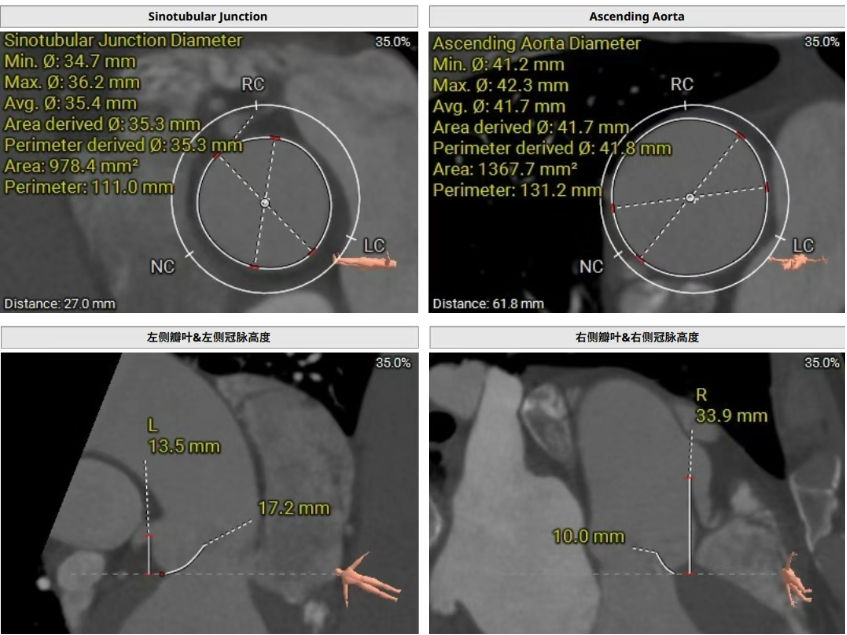

Preoperative CT evaluation showed that the patient had a tricuspid aortic valve with thickened leaflets. During diastole, prolapse of the right coronary cusp was observed, with mild calcification of that cusp. Three aortic sinuses were present and relatively evenly distributed. The perimeter-derived diameter of the aortic annulus was 28.0 mm. The perimeter-derived diameter of the left ventricular outflow tract (LVOT) was 29.5 mm, with no calcification or stenosis. The sinotubular junction (STJ) measured 35.3 mm in diameter, and the ascending aorta measured 41.8 mm. The coronary ostial heights were as follows: left coronary artery (LCA) 13.5 mm, with a leaflet length of 17.2 mm; right coronary artery (RCA) 33.9 mm, with a leaflet length of 10.0 mm. Mild calcification was noted in the left coronary artery. The patient had a horizontally oriented heart, with an angle of 135° between the left ventricle and the aorta.